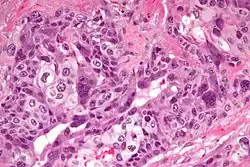

W obrazie mikroskopowym rak zarodkowy cechuje się zróżnicowanym wzorem utkania i często w obrębie jednego guza widoczne jest kilka wzorów architektonicznych[98]. Komórki nowotworowe mogą tworzyć wzór lity zbudowany ze ściśle ułożonych komórek w arkusze z obecnymi obszarami martwicy[98][101]. Wzór lity jest obecny niemal we wszystkich rakach zarodkowych[98]. Typ gruczołowy jest obecny w trzech czwartych przypadków raka zarodkowego, jest utworzony przez wytworzenie cewek, pęcherzyków lub gruczołów wyścielonych nabłonkiem sześciennym lub walcowatym[101]. Rzadszym wzorem jest typ brodawkowaty związany z obecnością w architekturze guza struktur brodawkowatych[101].

Tworzące rak zarodkowy komórki nowotworowe są niezróżnicowane, mają wygląd komórek nabłonkowych i przypominają komórki tworzące bardzo wczesny zarodek[99]. Komórki są duże, a niekiedy olbrzymie, wieloboczne, czasem walcowate[101][99]. Jądra komórkowe są duże, hiperchromatyczne, mają nieregularne, duże grudy chromatyny, występuje jedno lub więcej dużych jąderek[101][99][102]. Cytoplazma jest obfita, drobnoziarnista, bazofilna lub amfifilowa, rzadziej jasna[99][102]. Granice komórek są rozmyte[102]. Mitozy są liczne, często są obecne jej nieprawidłowe formy[103]. Na obrzeżach zmiany mogą być obecne komórki przypominające syncytiotrofoblast[102]. Ilość zrębu jest zmienna, w litym wzorze utkania jest skąpa, a na obrzeżach zmiany guz jest bardziej włóknisty, mniej lub bardziej komórkowy bez nacieku limfocytarnego[103]. W pozostałym miąższu jądra często obserwuje się wewnątrzprzewodową neoplazję komórek zarodkowych[102].